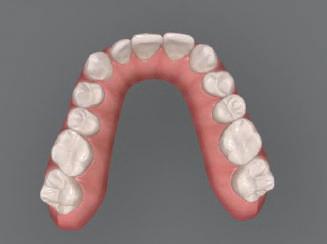

но

между членовете на екипа и пациента. ЗАКЛЮЧЕНИЕ Случаите на липсващи лате рални резци трябва да бъдат третирани от перспектива та на интердисциплинарна ди агностика и лечение. Употреба та на софтуера ClinCheck има доказани предимства за плани ране, комуникация между кли ницистите и пациента и фи нализиране на лечебния план, като се адресират всички же лания и притеснения на паци ента. Настоящият доклад на клиничен случай доказва, че с помощта на съвременните ме тоди един успешен екип от спе циалисти (ортодонт, консерва тивен зъболекар и хирург) може да се стреми към отлични ре зултати и да постига есте тични и функционални усмив ки без компромиси. Ред. бел.: Статията Treatment of a patient with a congenitally missing lateral incisor using aligners: A case report е пуб ликувана за първи път в сп. aligners–international magazine of aligner orthodontics, бр. 1, издание 1/2022. Библиографията е налична при издателя. За авторите: Д-р Iro Eleftheriadi завършва дентална медицина в Атинския университет, а магистратурата си по медицинска статистика – през 2014 г. в Публичния университет в Атина, Гърция. Специализира ортодонтия и завършва през 2017 г. в Университета в Тел Авив, Израел. Предстои ѝ да защити докторан тура във Факултета по дентална медицина към Университета в Атина, Гърция. Д-р Christodoulos Laspos завършва дентална медицина през 1995 г. в Атинския университет, Гърция, а магистратурата си завършва през 1999 г. във Фа култета по дентална медицина към Университета в Тенеси, Мемфис, САЩ. Печели стипендия и специализира лечение на пациенти с лицево-челюстни малформации в Университета в Тексас, Далас, САЩ, и е сертифициран специалист от Европейския борд на ортодонтите. Той е докторант в Универ ситета в Берн, Швейцария. От 2000 г. д-р Laspos практикува в частната си ортодонтска практика в Лимасол, Кипър. Той е основател и директор на MEDICLEFT, Кипърски център за цепки и лицево-челюстни аномалии, както и директор на фондацията Synergy, която осигурява следдипломно обучение на лекари по дентална медицина. Научен съ трудник е във Факултета по дентална медицина към Европейския университет в Кипър. Д-р Laspos изнася лекции по цял свят по теми като лицево-челюстни мал формации, ортогнатна хирургия, мултидисциплинарен подход и нови технологии в ортодонтията. Той е активен член на Европейското общество на Енгел и прези дент на Европейското ортодонтско общество. Фиг. 12а–c Финални странични (а и c) и фронтална интраорални снимки (b). Фиг. 13а и b Финални оклузални снимки. Фиг. 14 Финална снимка на усмивката отблизо. Фиг. 15 Финална екстраорална снимка на усмивката. Фиг. 16 Финална телерентгенография и цефалометричен анализ. Фиг. 12a Фиг. 13a Фиг. 14 Фиг. 15 Фиг. 16 Фиг. 13b Фиг. 12b Фиг. 12c клиничен случай с алайнери